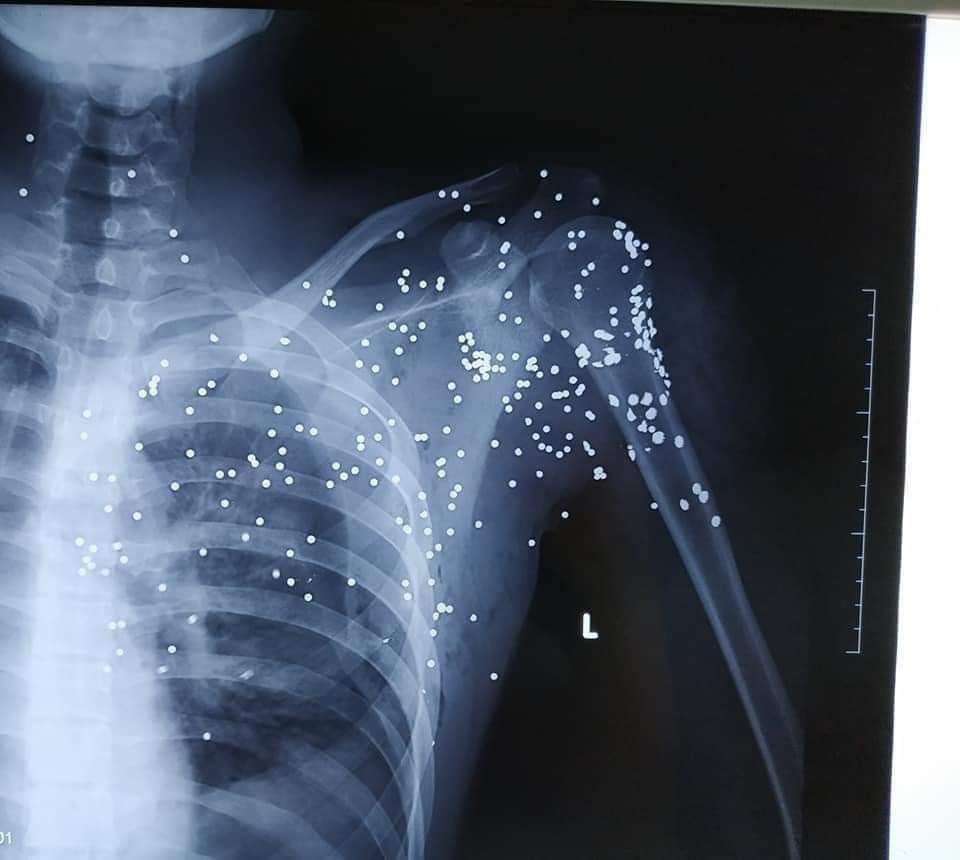

Vết đạn hoa cải dày trên người anh H. (Ảnh: Huy Hoàng) |

Anh H. được đưa đi cấp cứu tại Bệnh viện Đa khoa tỉnh Thái Bình trong tình trạng nguy kịch với nhiều vết đạn ở vùng cổ, vai và ngực trái.